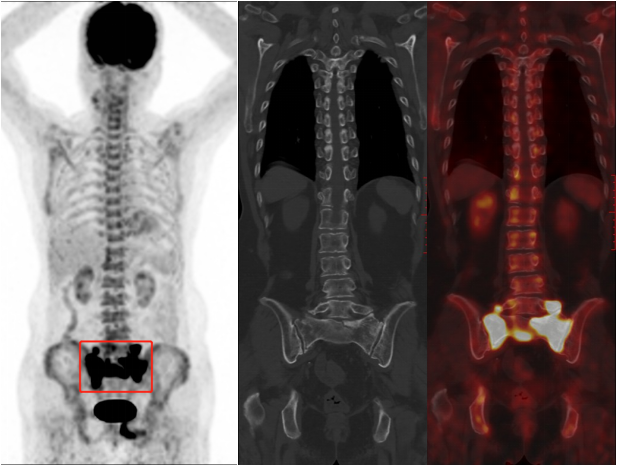

病例展示

患者女,79 岁,主诉骶尾部及左下肢疼痛近月余,无明确外伤史。外院 MRI 提示骶 1 椎体及左侧闭孔内肌异常信号,怀疑恶性肿瘤。既往无恶性肿瘤病史。为进一步明确骨病变性质行全身 18F-FDG PET/CT 显像,可见骶 1-2 椎体及骶 1-4 骶骨翼骨质不连续并见线样低密度影(骨折线),呈对称性 FDG 摄取显著增高,SUVmax 达 39.2,横向延伸至髂骨体,呈「H」形;另左侧耻骨体骨质不连续,见线样低密度影(骨折线),异常放射性浓聚。本例患者骶骨病变最大的特点为基本沿中线对称分布,骨质密度不均匀增高,占位效应不明显,FDG 摄取增高区呈特征性「H形 」分布。

基于骨病变代谢显著升高,对该患者来说,最重要的是除外恶性肿瘤(包括原发骨肿瘤和骨转移瘤),这也是患者做 PET/CT 的目的所在。若为骨转移瘤,PET/CT 未见原发恶性肿瘤征象,不支持;而原发骨肿瘤多呈溶骨性骨质破坏伴软组织肿块形成;以上改变均与本例患者影像表现不符。

有经验的影像医师应该会考虑到一个病:骶骨机能不全骨折,结合患者为绝经后老年女性(好发年龄),易有骨质疏松背景(危险因素),且左侧耻骨体骨折明确,因此考虑左侧耻骨体及骶 1-2 椎体、骶 1-4 骶骨翼均为机能不全骨折。